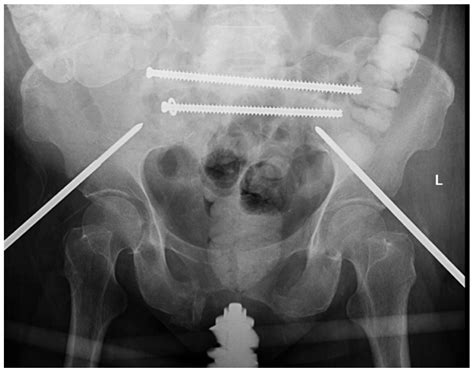

• Sacral Screw Fixation: A minimally invasive technique where screws are placed under fluoroscopic guidance to bridge the fracture site.

• Sacral Plate Fixation: Used for more complex or multi-fragment fractures to provide rigid internal stabilization.